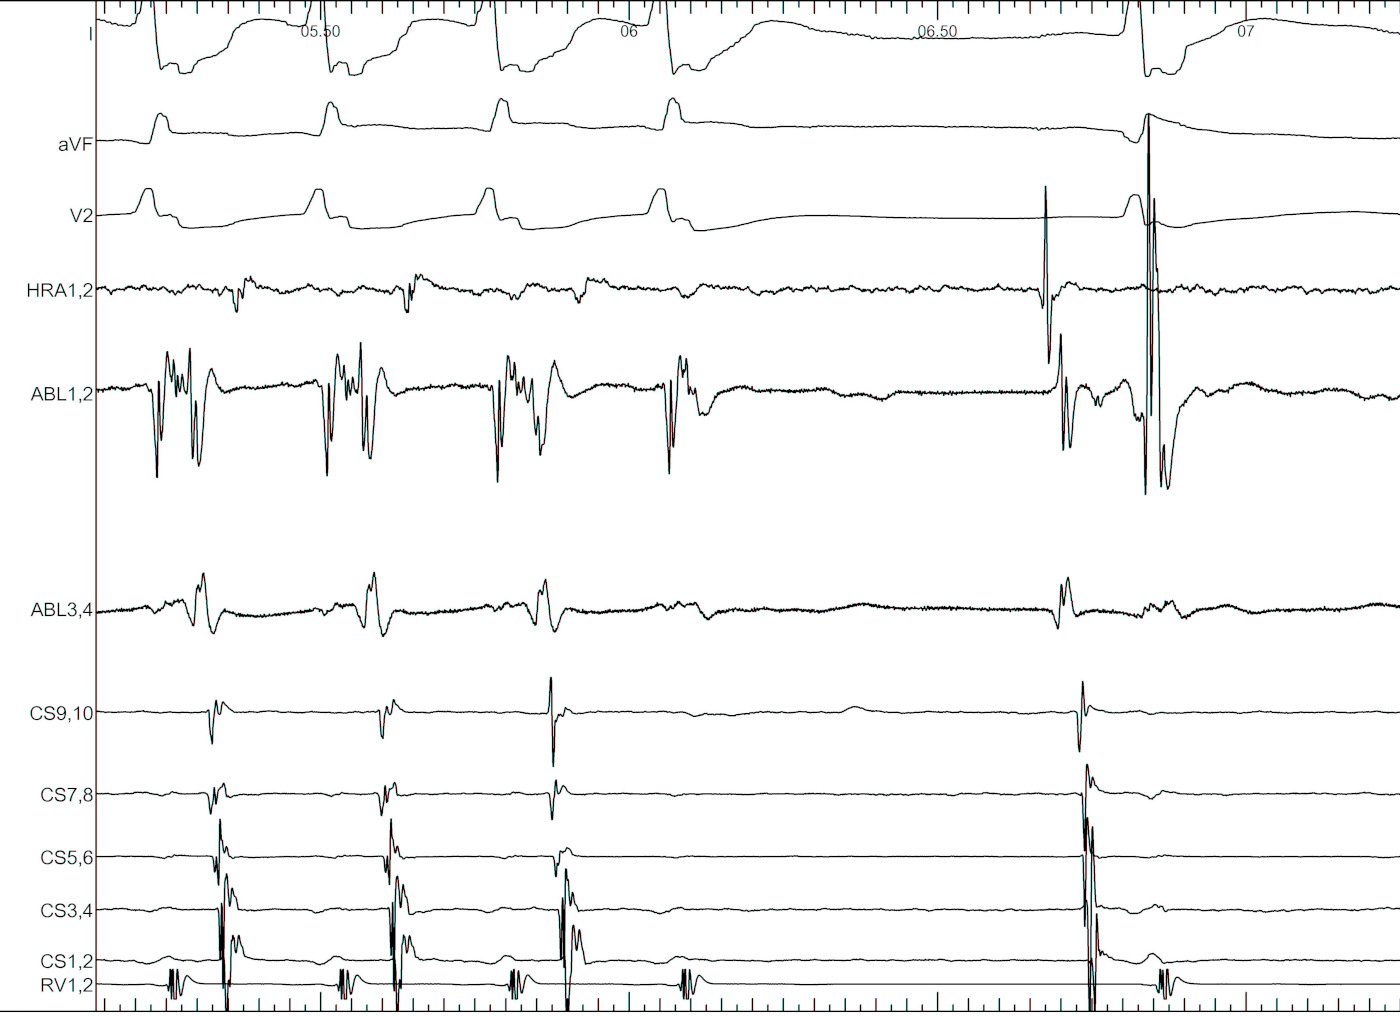

Identify components of the signal

mask1.jpg

mask2.jpg

mask3.jpg

mask4.jpg